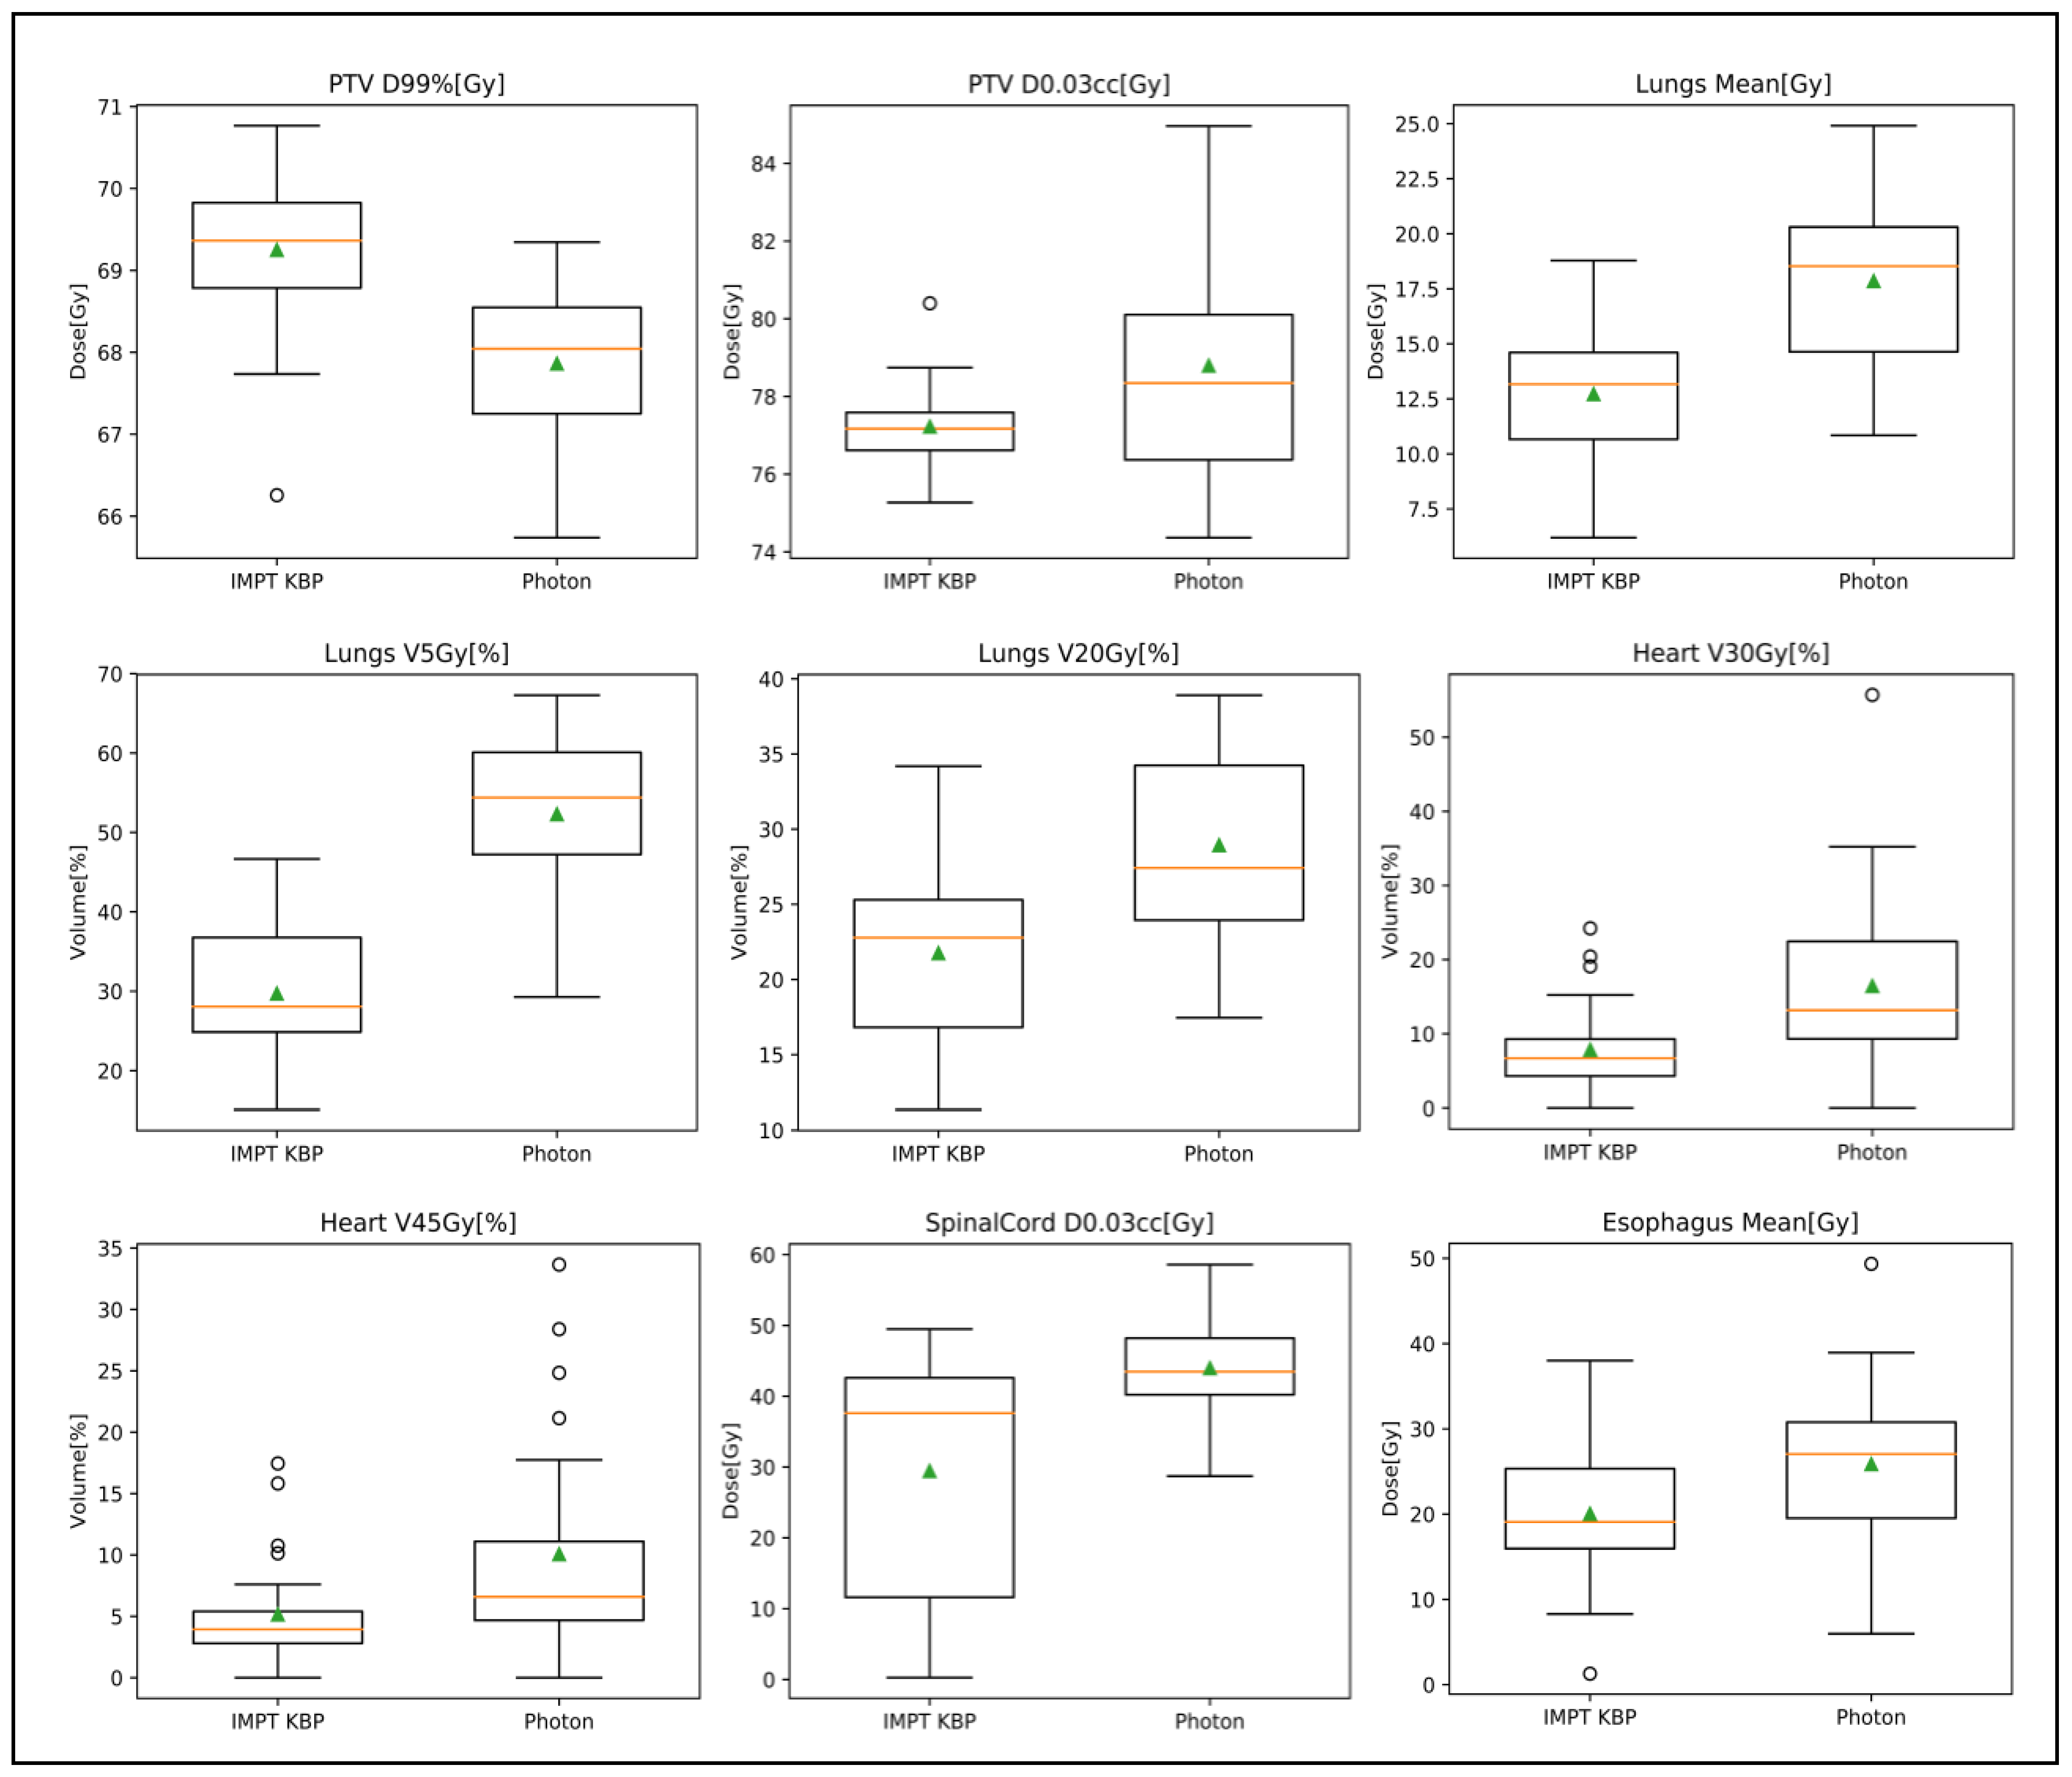

3.3.1. Photon Plan Quality Review

3.3.2. Proton Plan Quality Review

| Structure Name | Dose Point | Photon Original | IMPT KBP | p Value |

|---|---|---|---|---|

| PTV | D95%[Gy] | 70 | 70.91 ± 0.52 | <0.001 |

| D0.03cc[Gy] | 78.80 ± 3.06 | 77.23 ± 1.16 | 0.0246 | |

| D99%[Gy] | 67.86 ± 0.98 | 69.25 ± 0.97 | <0.001 | |

| Heart | V45Gy[%] | 10.1% ± 9.2% | 5.2% ± 4.7% | 0.00166 |

| V30Gy[%] | 16.5% ± 12.9% | 7.8% ± 6.5% | <0.001 | |

| Mean[Gy] | 14.02 ± 8.66 | 5.80 ± 4.42 | <0.001 | |

| Lungs | V5Gy[%] | 52.3% ± 10.1% | 29.7% ± 8.2% | <0.001 |

| V20Gy[%] | 28.9% ± 6.2% | 21.8% ± 5.6% | <0.001 | |

| Mean[Gy] | 17.85 ± 3.69 | 12.72 ± 3.43 | <0.001 | |

| Esophagus | V74Gy[cc] | 0.20 ± 0.45 | 0.03 ± 0.06 | N/A |

| Spinal cord | D0.03cc[Gy] | 43.97 ± 7.04 | 29.44 ± 16.81 | <0.001 |